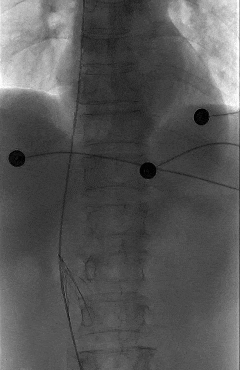

一切准备就绪后,田轩带领介入诊疗团队为阿婆实施下腔静脉滤器取出术。

术中,团队在影像设备的精准引导下,娴熟操作介入器械,精准定位倾斜的滤器,避开血管周边组织,逐步完成滤器的调整、抓取与取出操作。

整个手术过程十分顺利,未出现任何血管损伤等意外情况,这枚让阿婆和家属忧心许久的“困难”滤器被成功取出,术后阿婆生命体征平稳,身体状况良好。